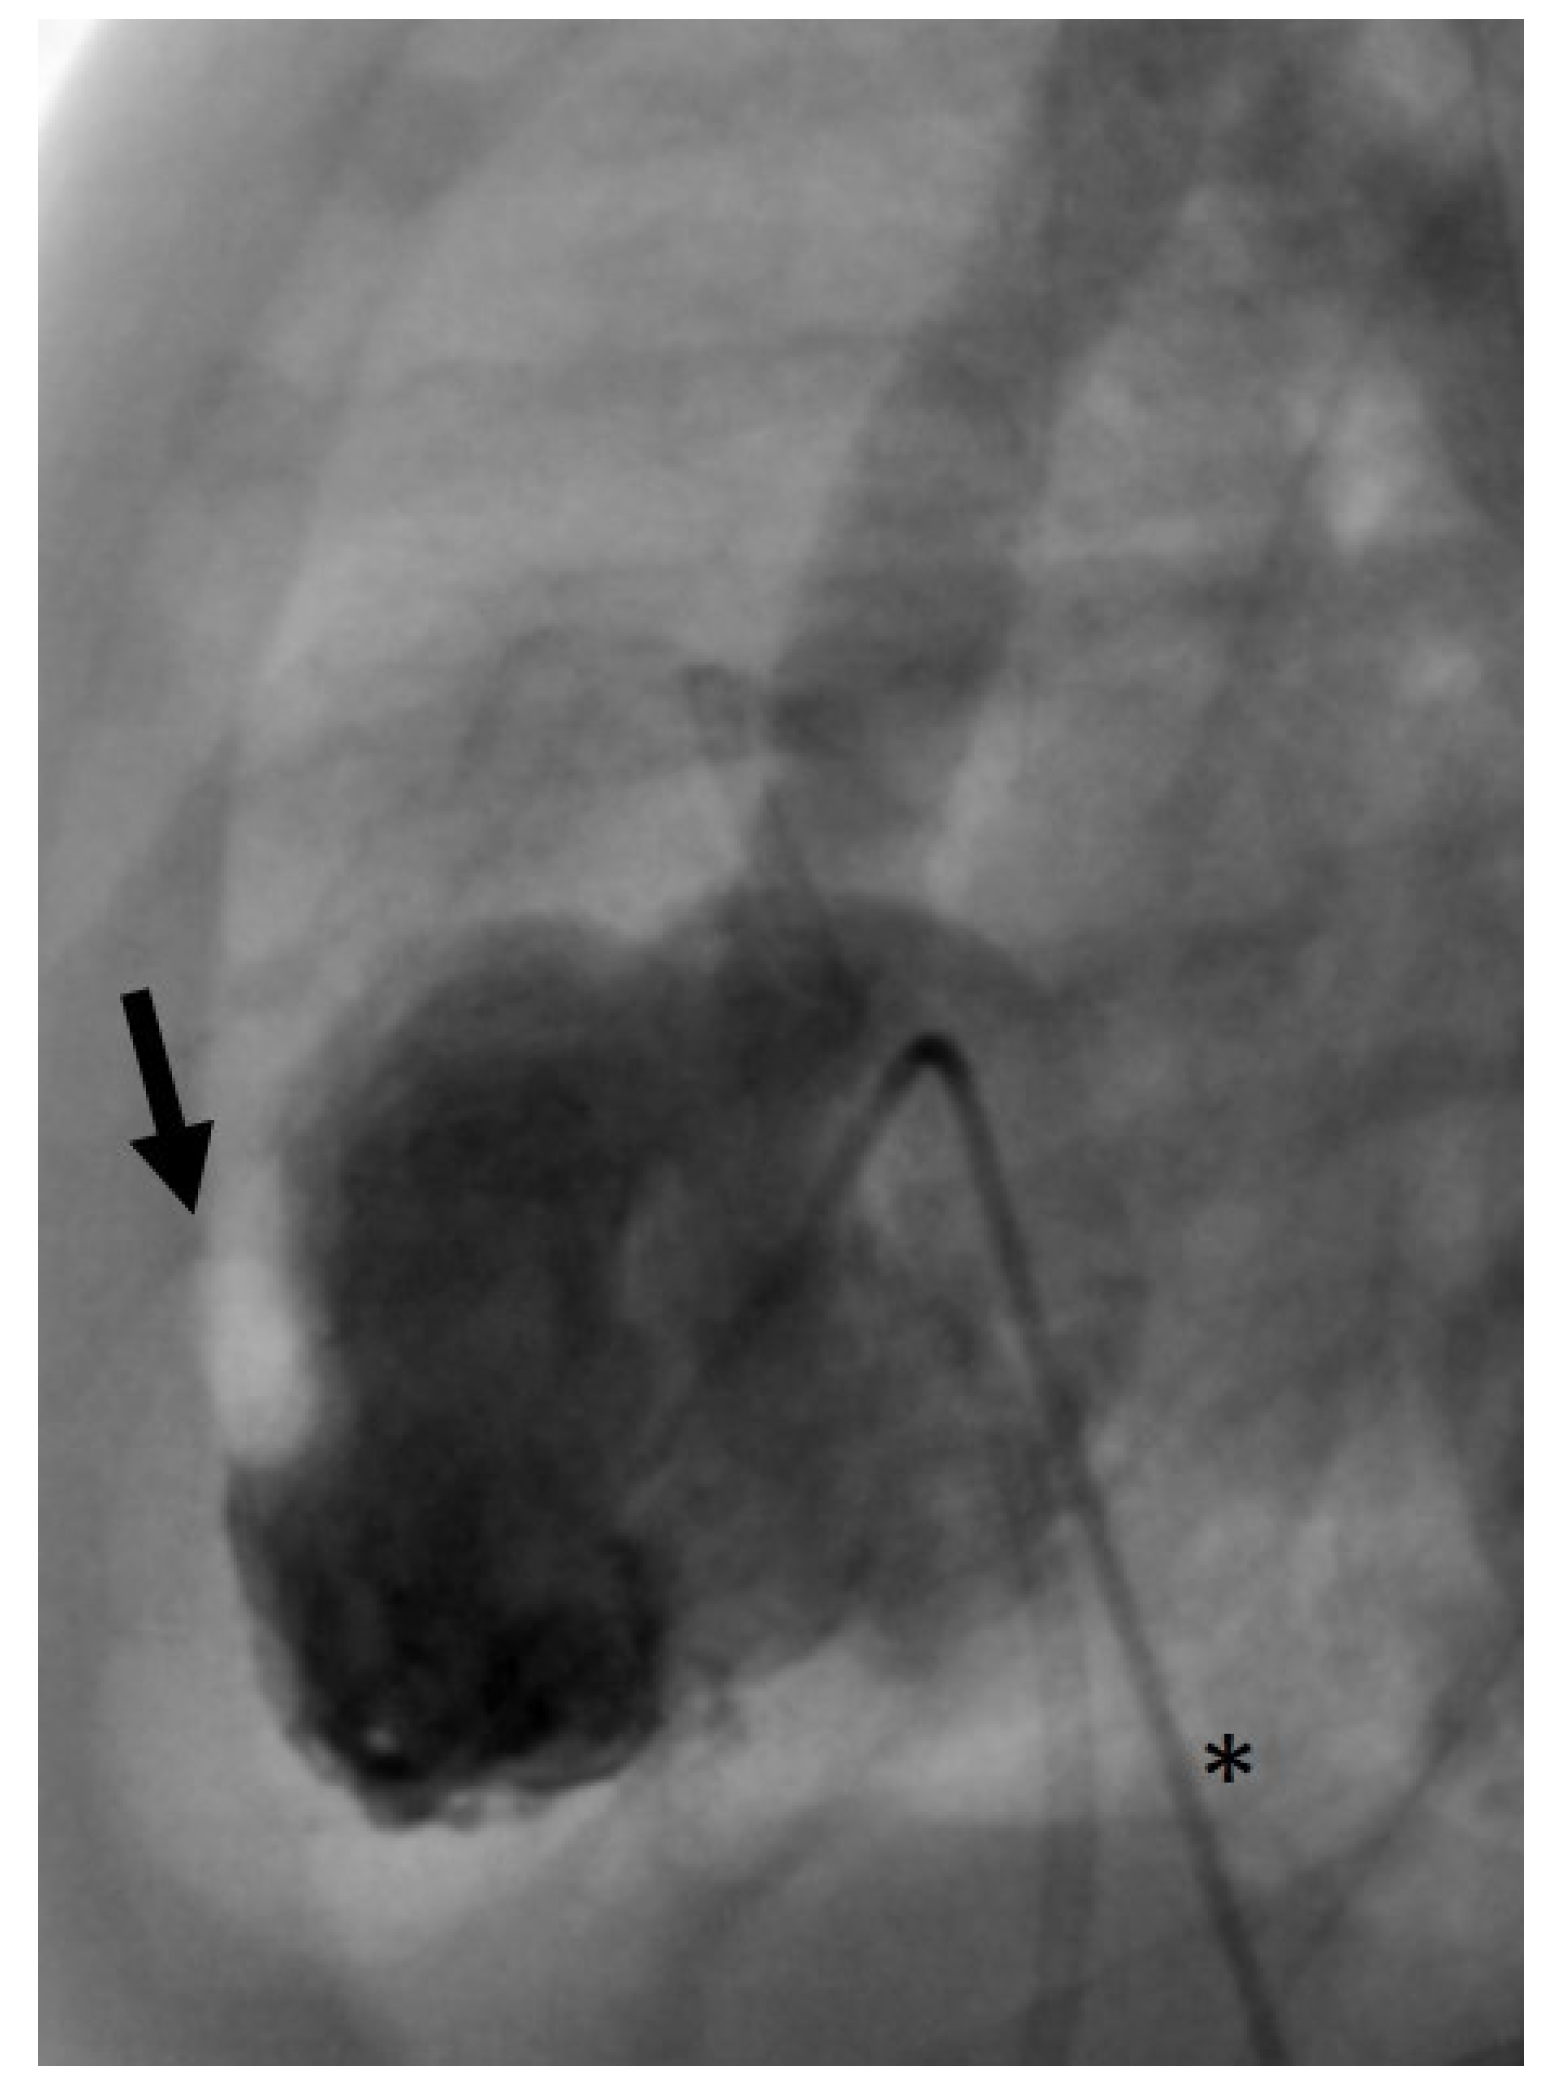

2.2. Percutaneous Catheterization

Femoral venous and arterial access was chosen in all patients. 4 French introducer sheaths and 4 French angiographic catheters (Multipurpose A SPECIAL, Cordis©, Miami Lakes, FL, USA) were used. First, we aimed at trans-arterial retrograde probing of the AV using a coronary guidewire. If this was successful, it may still have been difficult to pass the severely stenotic AV orifice with the angiographic catheter. In these cases, a 2.7 French microcatheter (Rebar™ 18, ev3 Neurovascular, Irvine, CA, USA) was introduced beforehand in order to provide more support for the angiographic catheter and thus to allow its trans-valvular passage. For retrograde BAV, the guidewire usually can be positioned stably within the LV (Figure 1).

Figure 1. Angiography of balloon aortic valvulotomy (BAV) with retrograde access (posterior-anterior projection). A trans-aortic guidewire (arrow) is inserted deep into the LV to ensure stable balloon support during BAV. The asterisk marks a gastric tube.